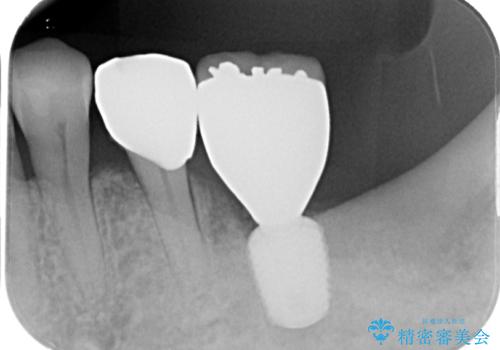

- ブリッジの土台から膿が出るとのことで来院された患者様です。

不均衡で無理な力がかかってしまうブリッジを装着したため、最後臼歯周辺の歯槽骨が溶けている状態でした。

上顎は最後臼歯が欠損しているため、ブリッジの土台は抜歯し、元々の欠損部にインプラントによる補綴治療を行うこととしました。

支台歯の骨欠損は予想以上に大きく、即時荷重インプラント部への影響が心配されましたが、無事に最短期間で治療を終えることができました。